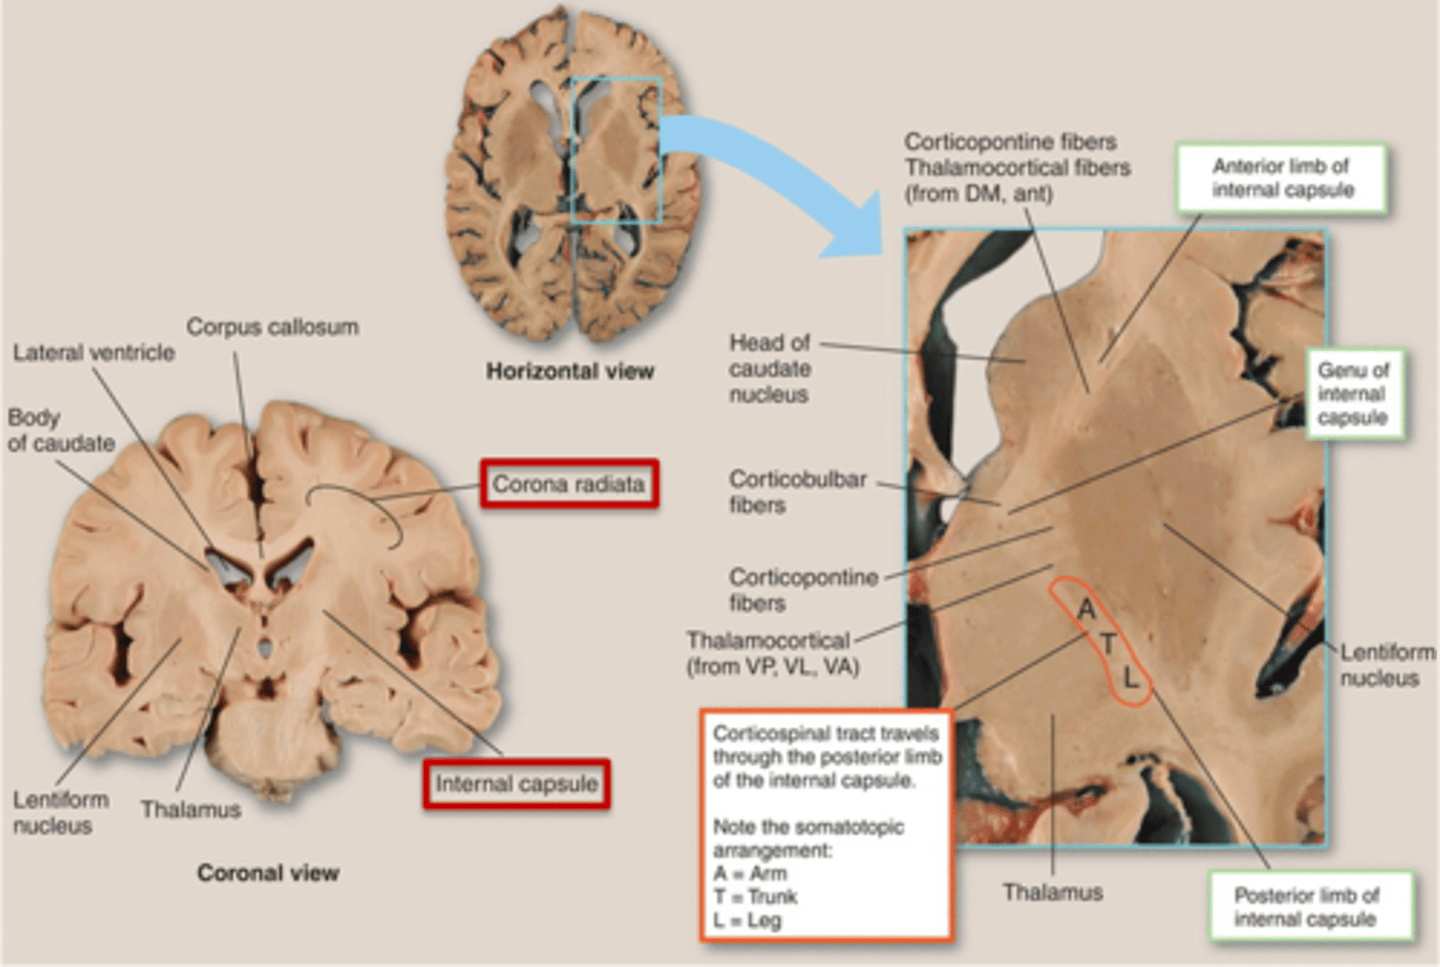

what are 3 key white matter structures found in the cerebrum?

1. corpus callosum

2. corona radiata

3. internal capsule

what cerebral white matter structure is a large bundle of nerve fibers that connects the left and right cerebral hemispheres, allowing them to communicate?

corpus callosum

what is the fan-shaped cerebral white matter sheet that is continuous ventrally with the internal capsule?

corona radiata

what cerebral white matter structure is a tract that carries sensory and motor information to and from the cerebral cortex?

internal capsule

what cerebral white matter structure is found between the basal ganglia?

internal capsule

what are the 3 regions of the internal capsule?

1. anterior limb

2. genu

3. posterior limb

what are the 3 parts of the basal ganglia? what runs between them?

1. caudate nucleus

2. putamen

3. globus pallidus

internal capsule

what part of the basal ganglia is the C-shaped structure that is most medial?

caudate nucleus

what part of the basal ganglia is medial to the putamen?

globus pallidus

the putamen and globus pallidus of the basal ganglia are collectively called the _______________ nucleus

lentiform